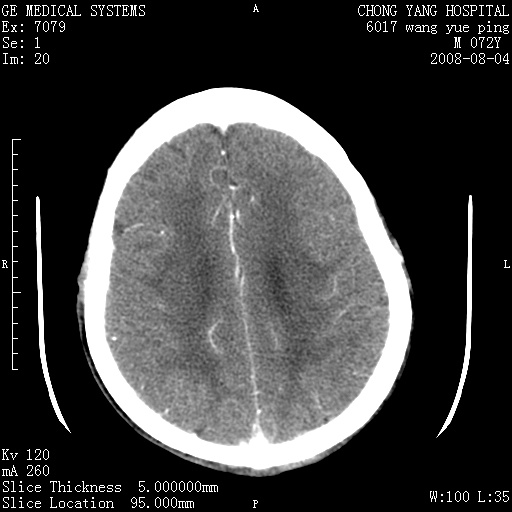

标题: CT14987:M72Y,头痛头昏,BP220/110. [打印本页]

标题: CT14987:M72Y,头痛头昏,BP220/110.

1)考虑左侧小脑脑梗塞。2)脑白质病。3)脑萎缩。4)双侧鼻腔新生物(息肉?)并阻塞性副鼻窦炎。

1.左侧小脑大面积梗塞;2.左侧基底节区腔梗;3.白质疏松;4.脑萎缩;5.慢性副鼻窦炎

小脑左侧病灶呈扇形分布,增强后未见明显瘤体样节结影,病变区未见强化。

支持:左侧小脑脑梗塞梗塞表现

另:脑白质病。脑萎缩。双侧鼻腔新生物(息肉?)并阻塞性副鼻窦炎。

1)考虑左侧小脑脑梗塞,建议治疗后复查除外其他,左基底节区腔隙性脑梗塞2)脑白质变性3)脑萎缩。4)双侧鼻腔新生物(息肉?)并阻塞性副鼻窦炎。